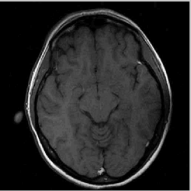

The reconstructions of a 256×256256256256\times 256 brain image from its radial samples acquired with a 40 spoke trajectory are shown in Fig. 6. The measurements are corrupted with zero mean complex Gaussian noise of standard deviation σ=18.8𝜎18.8\sigma=18.8. All methods result in loss of subtle image features since the acceleration factor and the noise level are high. We observe that the NLS scheme provides better recovery than the competing methods. The quantitative results in this setting for various MR images are shown in the bottom section of Table IV. We observe that the SNR improvement offered by NLS over the other methods are not as high as in the previous cases, mainly due to the considerable noise in the data and the high acceleration.

Refer to caption

(a) Original

(b) DLMRI,SNR=17.46

(c) TV,SNR=17.43

(d) NLS,SNR=18.46

(e) Sampling pattern

(f) DLMRI error

(g) TV error

(h) NLS error

Figure 6: Comparison of the algorithms in the presence of noise. We consider the recovery of a 256×256256256256\times 256 original MRI brain image from its radial trajectory with 40 spokes, contaminated by Gaussian noise with standard deviation σ=18.8𝜎18.8\sigma=18.8. The error images are magnified by a scale of 5 fold for the best visibility. This is a challenging case due to the high undersampling factor and high measurement noise. We observe that the NLS scheme provides the best overall reconstructions.